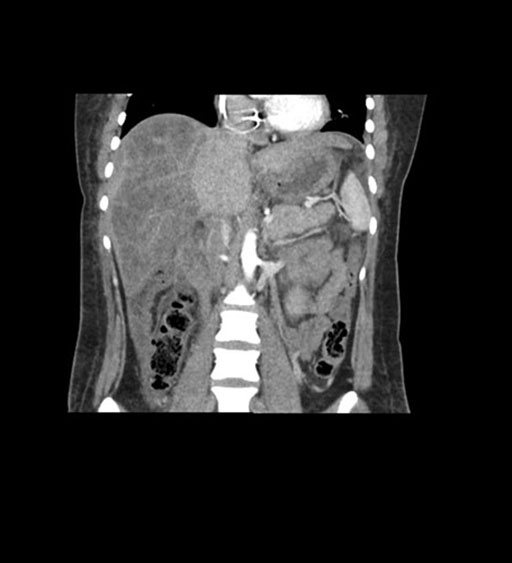

Coronal Arterial